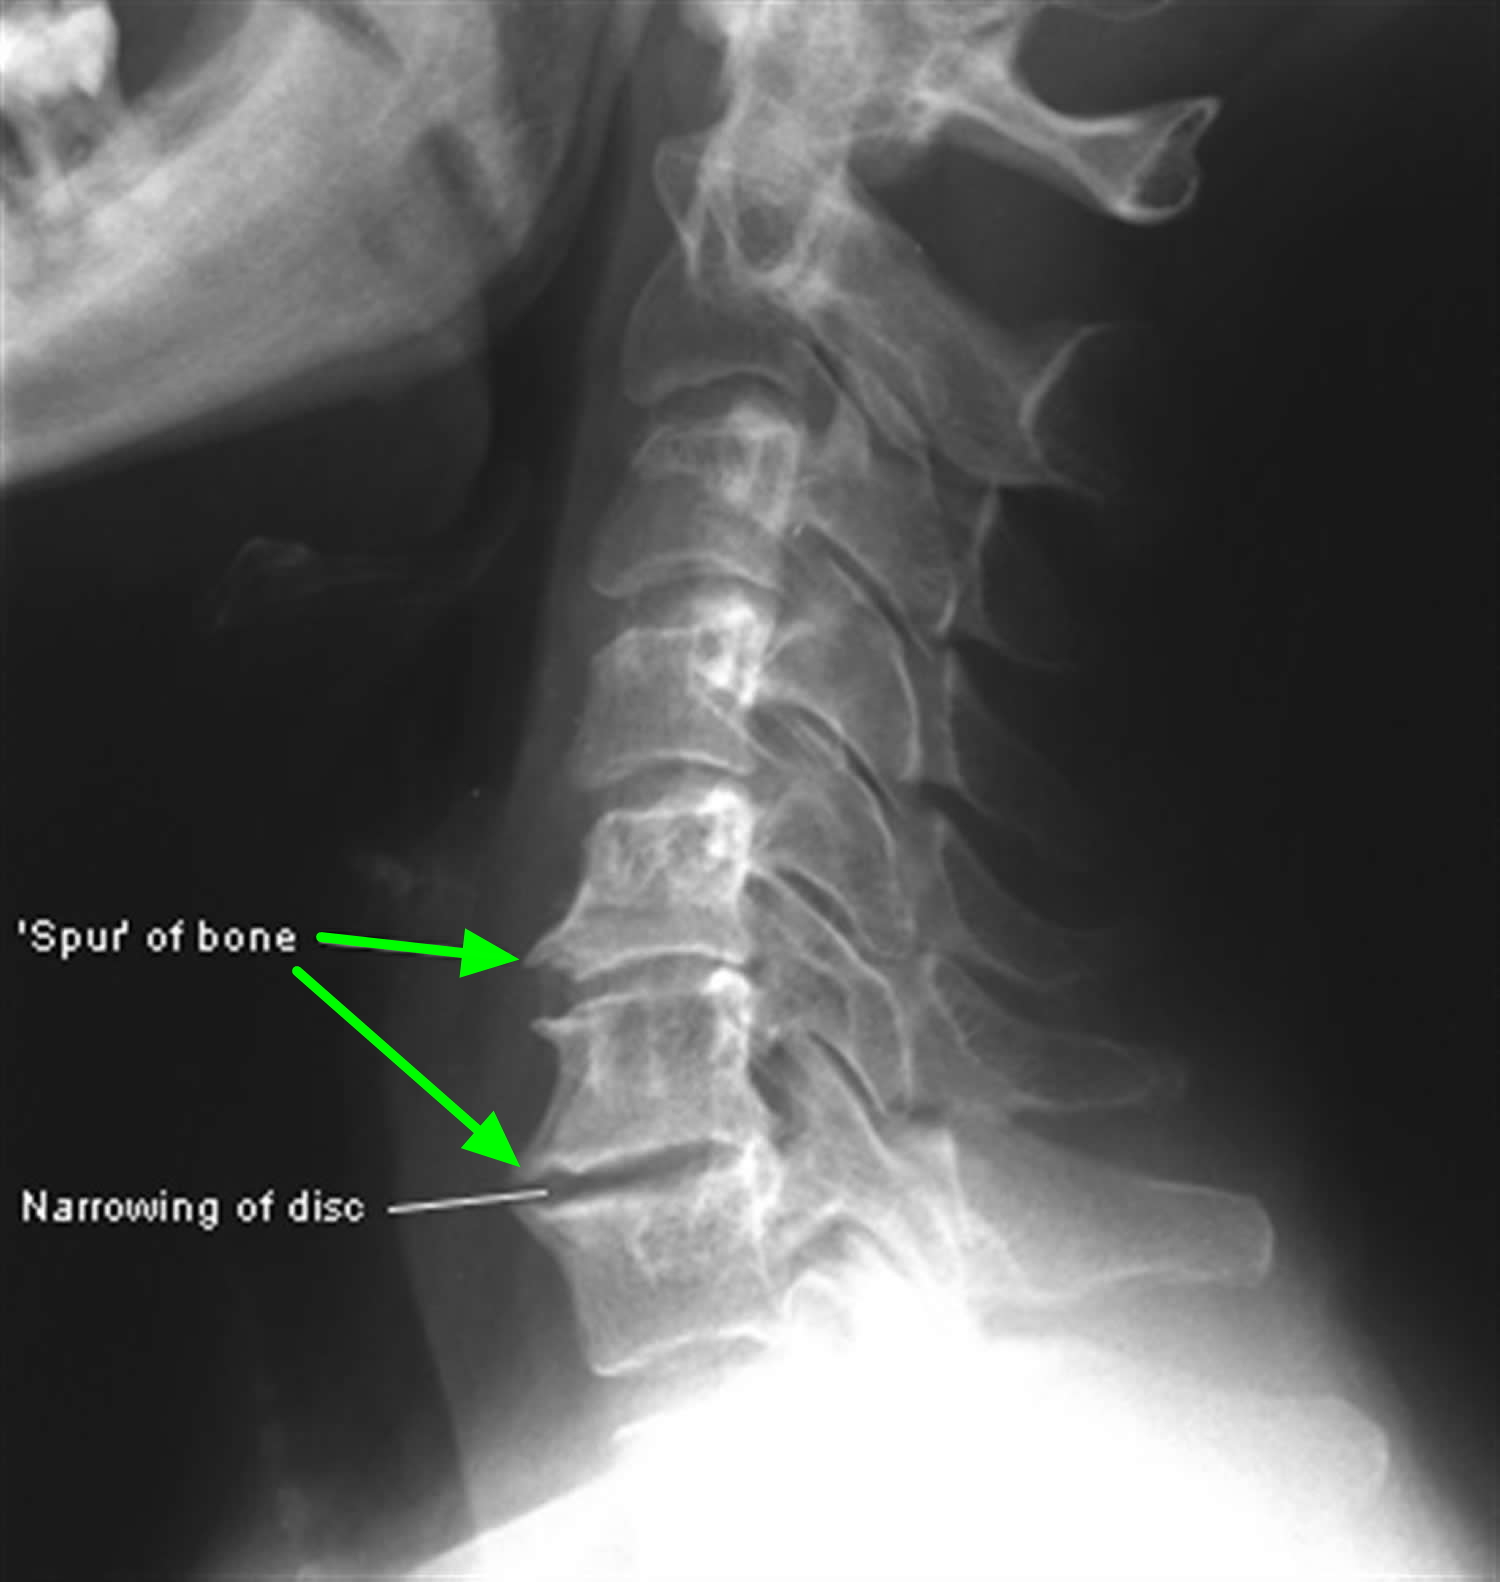

Learn about osteophytes in cervical vertebrae, commonly known as bone spurs. Discover the causes, symptoms, and effective treatment options for this neck condition. Understand how cervical spondylosis and degenerative disc disease impact your spinal health, and find expert advice on managing pain, improving mobility, and exploring non-surgical solutions to relieve pressure on your nerves and improve your quality of life.

Read full article: Osteophytes In Cervical Vertebrae